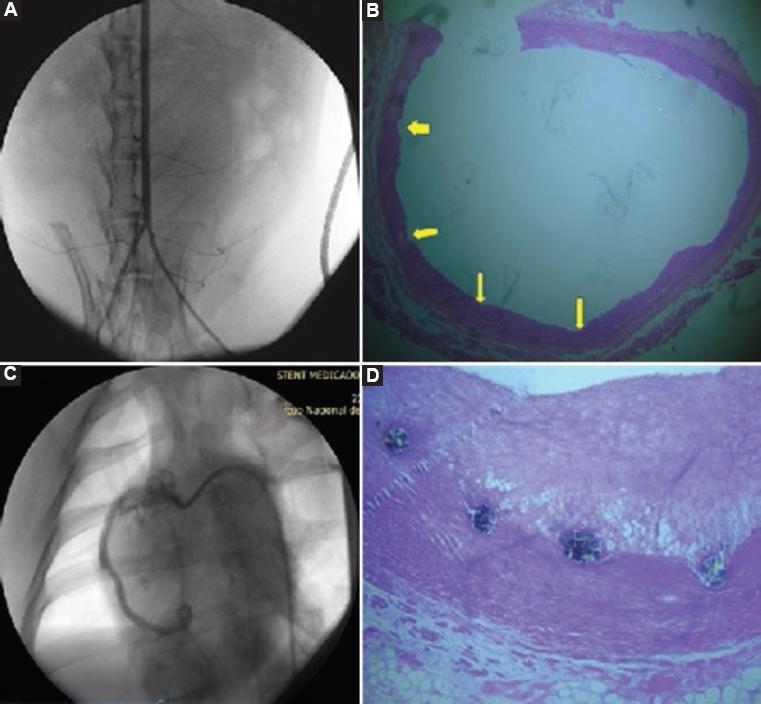

The rabbit aorta was longitudinally dissected for stent extraction. Neo-intimal proliferation and data consistent with inflammation or bleeding were not observed. The INC D1 stent showed high capacity to inhibit cell proliferation and inflammation. The INC-D2 stent was removed by cross section of the pig coronary artery. The stent struts were observed to be dark brown in color, in oval or round arrangement in the intima-smooth muscle transition zone. There was accentuated proliferation of the intima on the stent. The struts were partially attached to the muscle layer, which was slightly sclerosed, and were projected towards the fibrous intima, with scarce lipids in the form of drops or circumferences. The INC D2 stent showed no power to inhibit neointimal proliferation with the drug concentration used in the porcine model (Fig. 3).

Figure 3 Angiography and histopathological images of the animal models. A and B) Leporid model in which percutaneous left femoral access was carried out. The angiography shows vascular integrity of the aorta with the INC-D1 stent (sirolimus) and the photomicrography of the rabbit aorta shows the notches (yellow arrows) left by the INC-D1 stent (sirolimus) struts, without neointimal proliferation . C and D) Porcine model. Angiographic image was obtained after implantation of the INC-D2 stent (paclitaxel) in the middle third of the pigs coronary artery. In the photomicrography of the pigs right coronary artery in cross section with the INC-D2 stent (paclitaxel), two struts are observed that are partially attached to the slightly sclerosed muscular layer and project to the fibrous intima with scarce lipids in the form of drops or circumferences (40 x).